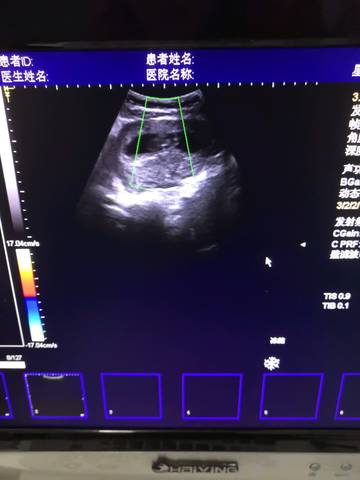

胎囊、胎芽、胎心到底是什么?

孕早期的前几周的准妈妈经常会看见“胎囊”、“胚芽”和“胎心”...多准妈妈不了解到底胎囊、胎芽、胎心是个啥...